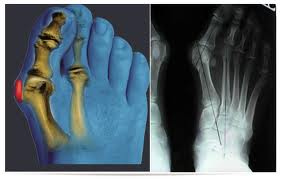

Диагноз не вызывает особых затруднений. Врач может диагностировать вальгусную деформацию большого пальца стопы уже при первом осмотре. Рентгенологическое обследование поможет установить характер костных деформаций, степень повреждения сустава и угловые отношения между первой и второй плюсневой костью. Следует назначить анализы крови и мочи для установления возможных метаболических нарушений.

Лечение преимущественно симптоматическое, направленное на устранение болевого синдрома. При выраженных деформациях производится хирургическое вмешательство. Раннее оперативное лечение ведёт к профилактике артроза в первом плюсне-фаланговом суставе и более благоприятным исходам операции. Современные хирургические методы не разрушают сустав, сохраняя его подвижность и опороспособность.

Медицинские процедуры: Операция на большом пальце стопыСпециальности по данному заболеванию